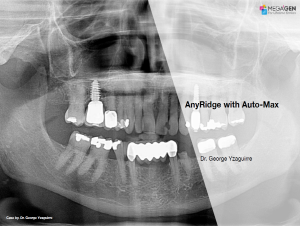

AnyRidge with Auto-Max

Dr. George Yzaguirre,Bone regeneration,Maxillary Posterior,#16,GBR,AnyRidge,Auto-Max,Clinical case

English

2019-10-01

PDF

587.67 Kb

Clinical cases

204